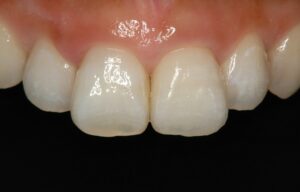

審美歯科

Case Studies